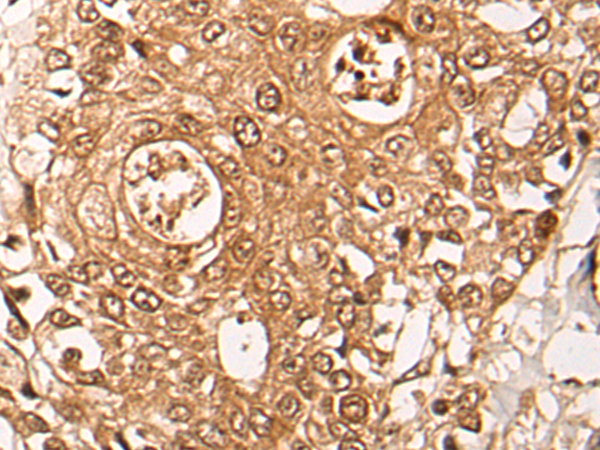

IHC (Immunohiostchemistry)

(The image on the left is immunohistochemistry of paraffin-embedded Human thyroid cancer tissue using 46722(ZPR1 Antibody) at dilution 1/40, on the right is treated with fusion protein. (Original magnification: x200))